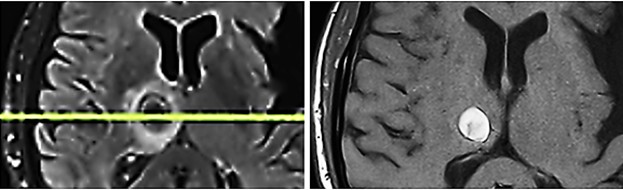

Fig. 5

Fig. 5: Metastasis in the right thalamus before transcranial TMI treatment with pronounced perifocal edema (left) and five months after TMI treatment; notably the brain tissue is not impaired by the transcranial TMI treatment (right).

After a period of complete pain and symptom relief, the patient experienced sudden and rapidly progressive paralysis of the left side of his body with a rapid loss of the ability to walk. Subsequently, significant deficits in spatial perception developed. Imaging of the skull revealed a suspected hemorrhagic metastasis in the region of the right precentral gyrus and another prominent metastasis in the region of the right thalamus. A neurosurgical decompression of the metastatic tumor in the right precentral gyrus was performed and provided histological confirmation of a metastasis of malignant melanoma. However, due to a rapid recurrence of paresis and an increase in the size of the thalamic metastasis, CyberKnife treatment of the affected area was performed. This also included the treatment of a newly developed right-sided cerebellar metastasis. After exhausting all conventional methods and experiencing severe intolerance to oral medication with Trametinib and Dabrafenib, the patient was bedridden with left-sided paresis and severely impaired consciousness in a palliative situation. Further imaging showed a progression of the thalamic metastasis as well as several small right-sided cerebellar metastases. The patient was given up expecting his imminent death. Therefore, transcranial TMI treatment has been administered as a last resort. Nine focused TMI treatments of the affected right thalamic area were performed twice weekly, using a combination of piezoelectric techniques with the PiezoWave2 device (penetration depth 40-50 mm, energy flux density 0.1-0.15 mJ/mm2 adjusted for tolerance, frequency 3 Hz, applying 600-200 impulses per session adjusted for tolerance) and electrohydraulic techniques with the OrthoGold100® device (light blue applicator, energy flux density 0.09–0.12 mJ/mm², frequency 2-4 Hz, alternating, impulses 500-1200 per session, each adjusted for tolerance in case of the patient's limited general condition). Following completion of the focused transcranial TMI treatment of the thalamic region, the area of the right-sided cerebellar metastasis was treated seven times in the same way with a combination of piezoelectric and electrohydraulic techniques. Prior to the treatments, curcumin infusions (150 mg per dose), an active constituent of the ancient medicinal herb Curcuma longa L., were administered twice weekly to support the immune system and to increase the efficiency of the electrohydraulic TMI treatment via a photosensitive effect. A total of 13 curcumin infusions were given. From the outset, all combined piezoelectric and electrohydraulic treatments were subsequently expanded with a gentle, putative neuro-regenerative treatment of the entire brain using circular movements around the skull exclusively applying electrohydraulic technology with the OrthoGold100® device, always unfocused, with higher frequencies and significantly lower power outputs, and with a comparatively higher number of dual-state pulses (yellow applicator, energy flux density 0.02–0.05 mJ/mm², frequency 3 Hz, impulses 1500-3000 per session), adjusted for tolerance. With temporary clinical improvement and increased patient tolerance, the established treatment of the pelvic bone metastasis using with the OrthoGold100® device was resumed (light blue applicator, energy flux density 0.23 mJ/mm², frequency 2 Hz, 2000 impulses per session). However, during the treatment, the patient became somnolent and had to be carefully supported at home with the assistance of the entire family. Apart from curcumin infusion therapy, life-sustaining fluid therapy, and TMI treatment, all other medications were discontinued, even the dexamethasone initially administered to reduce intracranial pressure.

After transcranial TMI treatment as described, the patient was becoming increasingly alert and showed improvement in all neurological investigations. With the support of the physiotherapist, he could now walk short distances and climb one flight of stairs, use the toilet independently, his spatial awareness was steadily improving, he could eat independently, and had complete recollection of all events up to the onset of somnolence. He had no memory of the eight weeks of somnolent state. A follow-up MRI of the skull shows the previously identified hemorrhagic area surrounded by a glial capsule and a perifocal edema, but no further progression of the metastasis. The TMI reated thalamic metastasis had shrunk considerably though it is unsure if there remained still vital tumorous tissue (Fig. 5). It must be underlined that the surrounding brain tissue was not impaired or damaged by TMI treatment, so that the patient clinically improved, unexpectedly gained again full neurological control, could leave the hospital and return home.